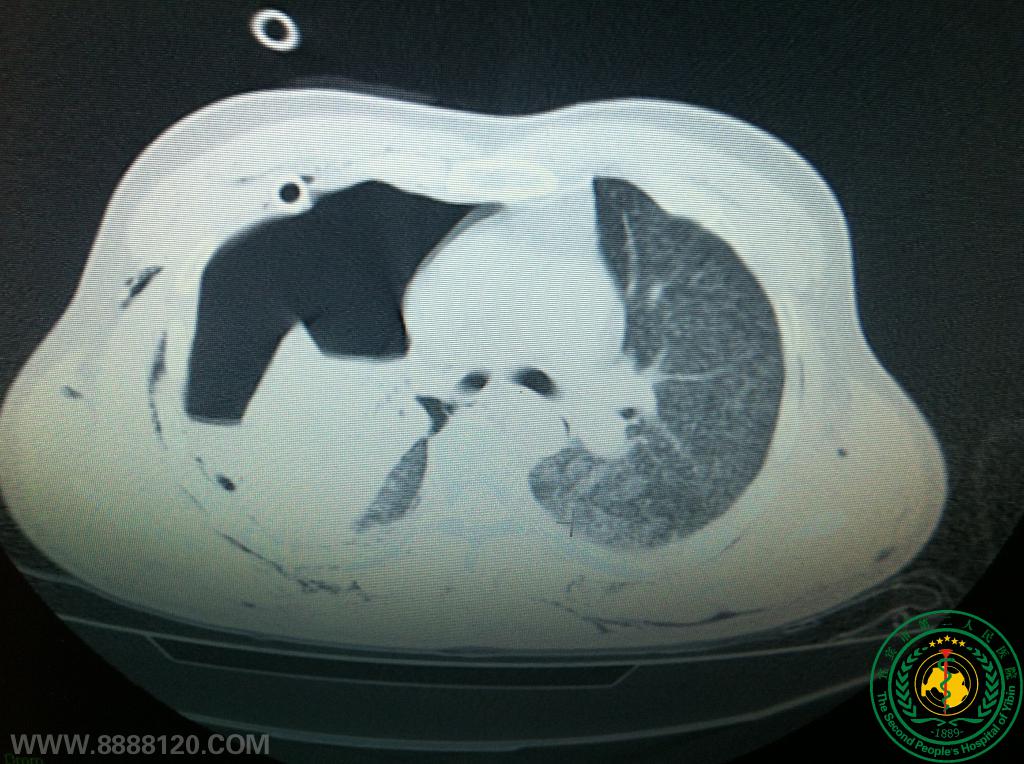

宜宾市第二人民医院胸心外科成功救治一名右肺上下叶支气管完全断裂重伤员(右上叶支气管发育异常)

宜宾市第二人民医院胸心外科成功救治一名右肺上下叶支气管完全断裂重伤员(右上叶支气管发育异常)6175